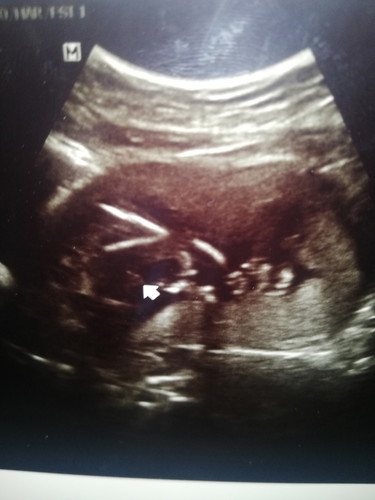

ซาวน์ครั้งแรก ?? ท้องแรก

เพิ่งไปซาวน์มาเมื่อตอนเย็นวันนี้ ครั้งแรกเลยจ้า ผมไม่อายเลยครับบบบ โผล่มาเต็มๆให้เห็นเลย ❤️?

บ้านนี้เห็นชัดเหมือนกันคะ